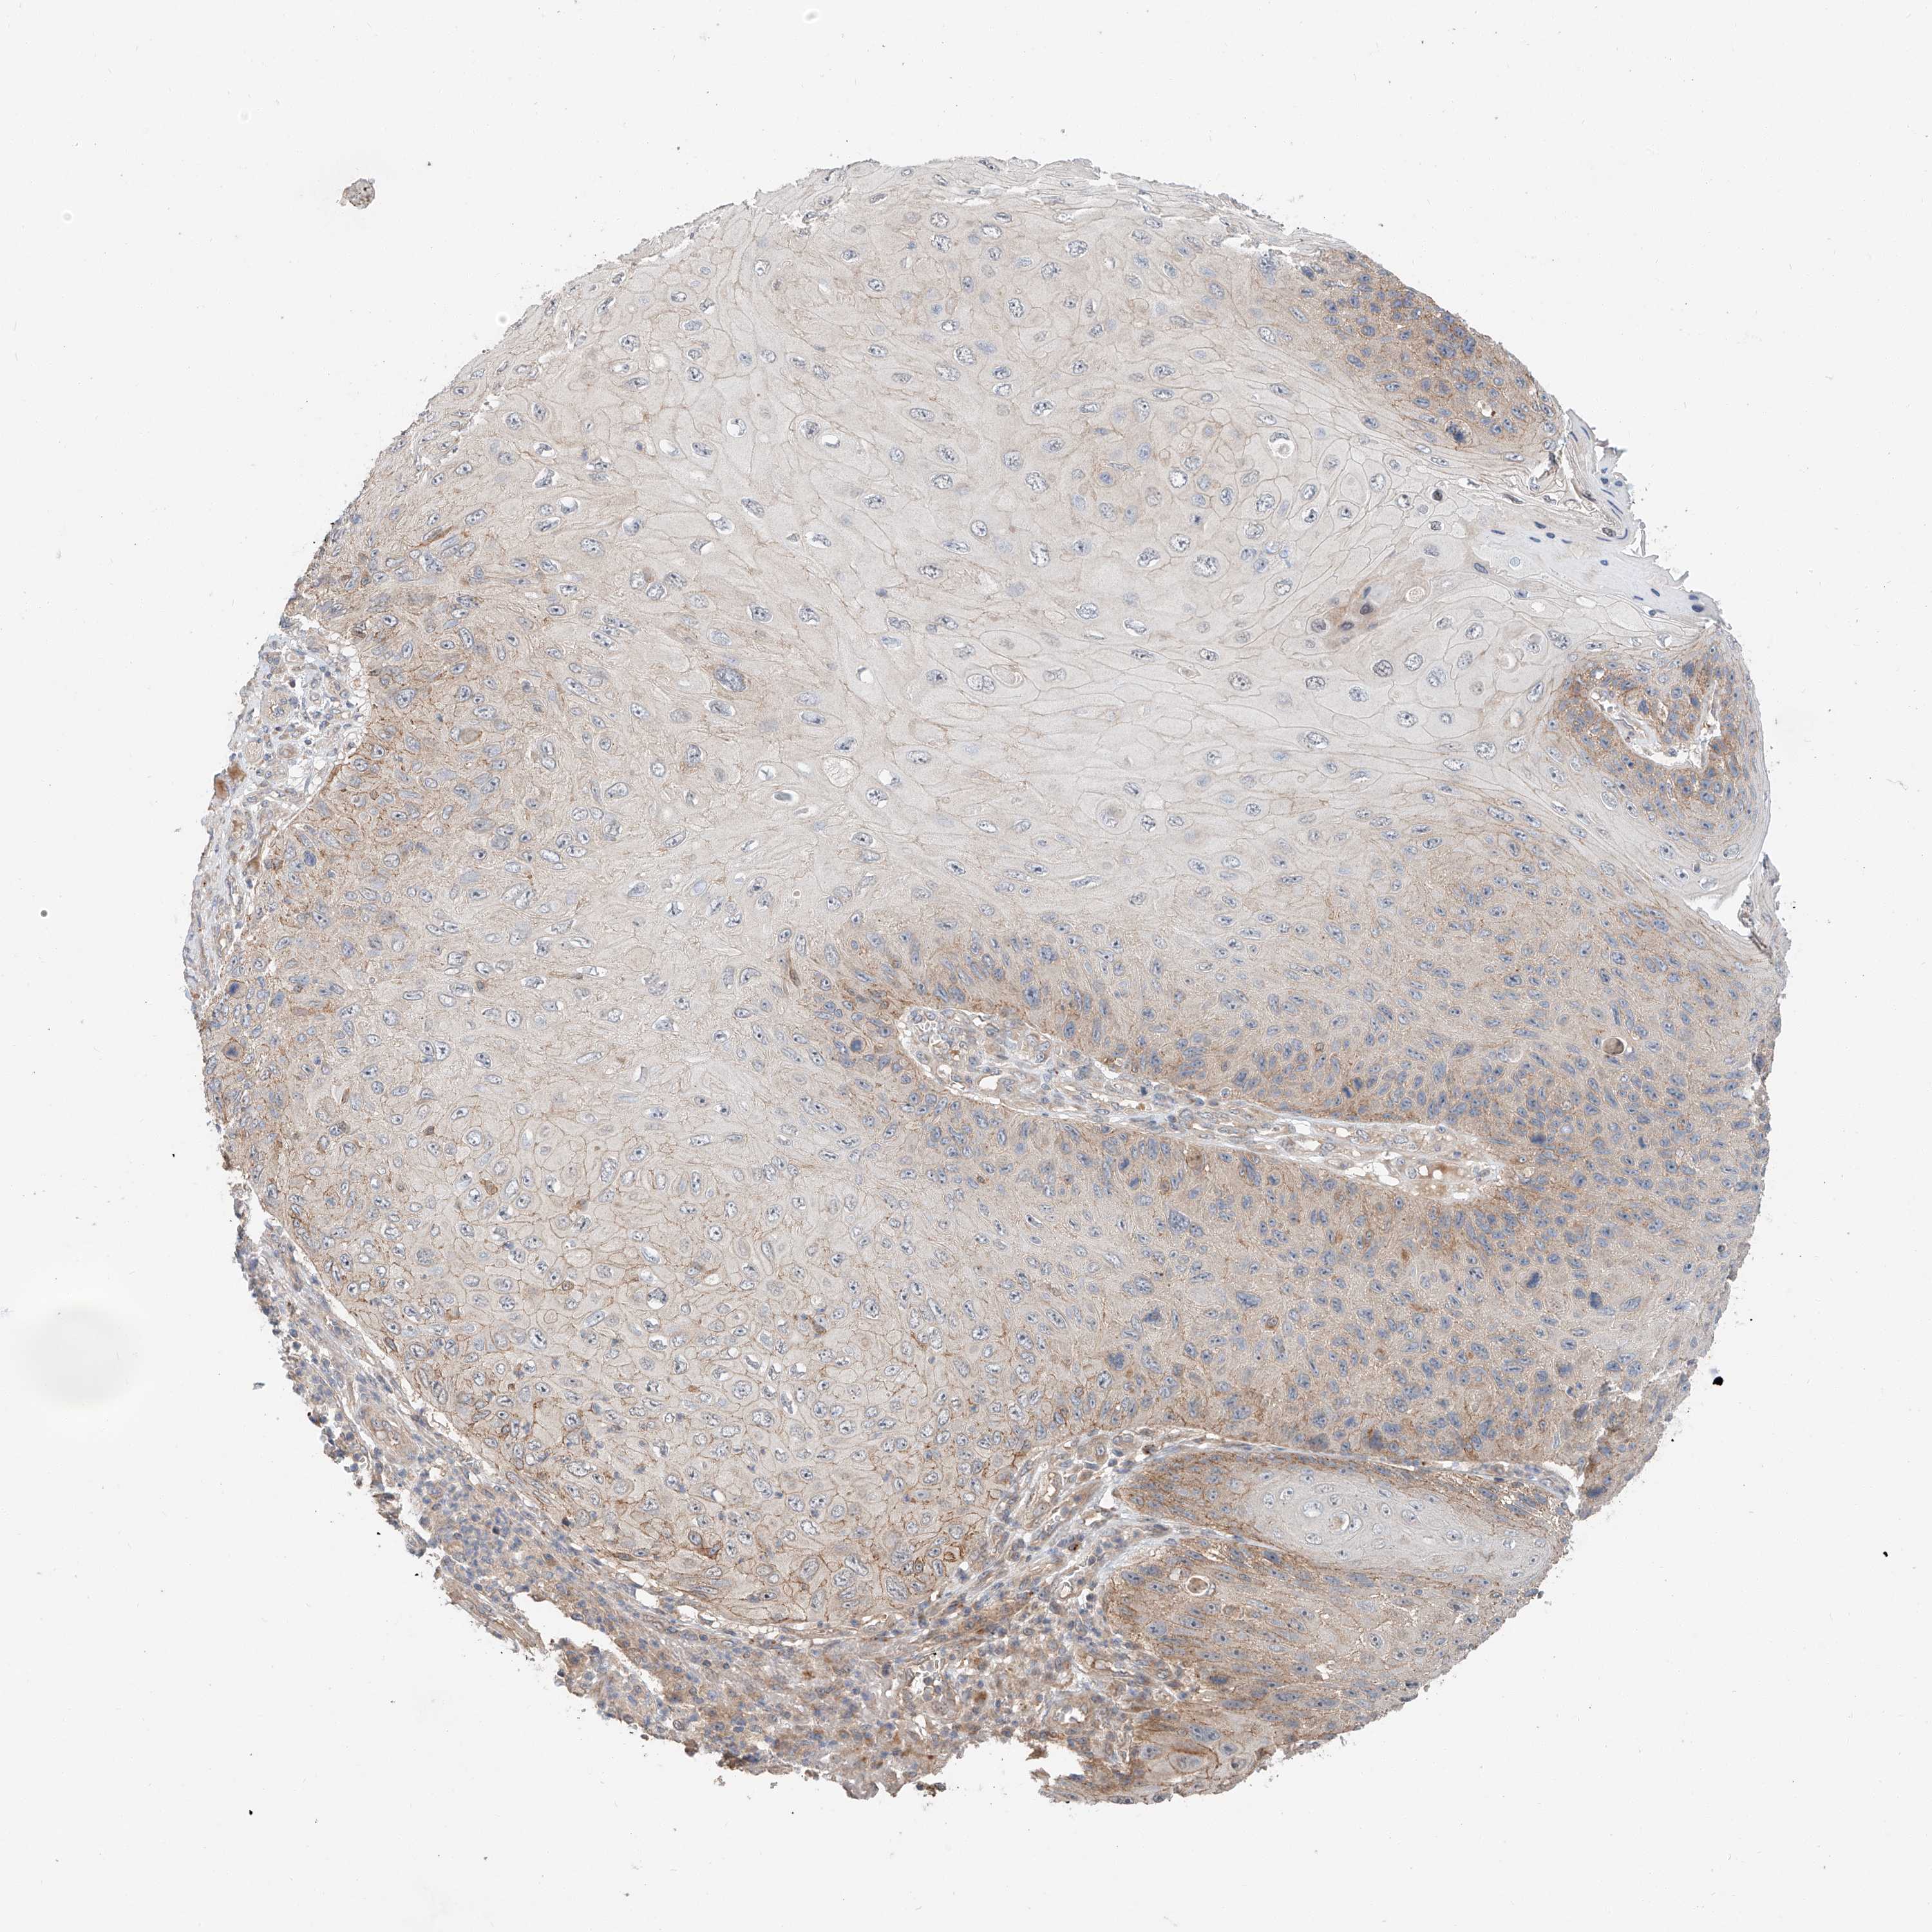

CANCER SKIN CANCER Show tissue menu

SKIN CANCER - Protein expressioni

A mouse-over function shows sample information and annotation data. Click on an image to view it in a full screen mode. Samples can be filtered based on level of antibody staining by selecting one or several of the following categories: high, medium, low and not detected. The assay and annotation is described here.

Antibody stainingi

Antibody staining in the annotated cell types in the current human tissue is reported as not detected, low, medium, or high, based on conventional immunohistochemistry profiling in selected tissues. This score is based on the combination of the staining intensity and fraction of stained cells.

Each image is clickable and will lead to virtual microscopy that enables deeper exploration of all samples and also displays staining intensity scores, fraction scores and subcellular localization as well as patient and tissue information for each sample.

HPA030419

HPA030420

HPA030422

CAB025196

CAB080286

CAB080287

Basal cell carcinoma

Squamous cell carcinoma, NOS

Squamous cell carcinoma, metastatic, NOS